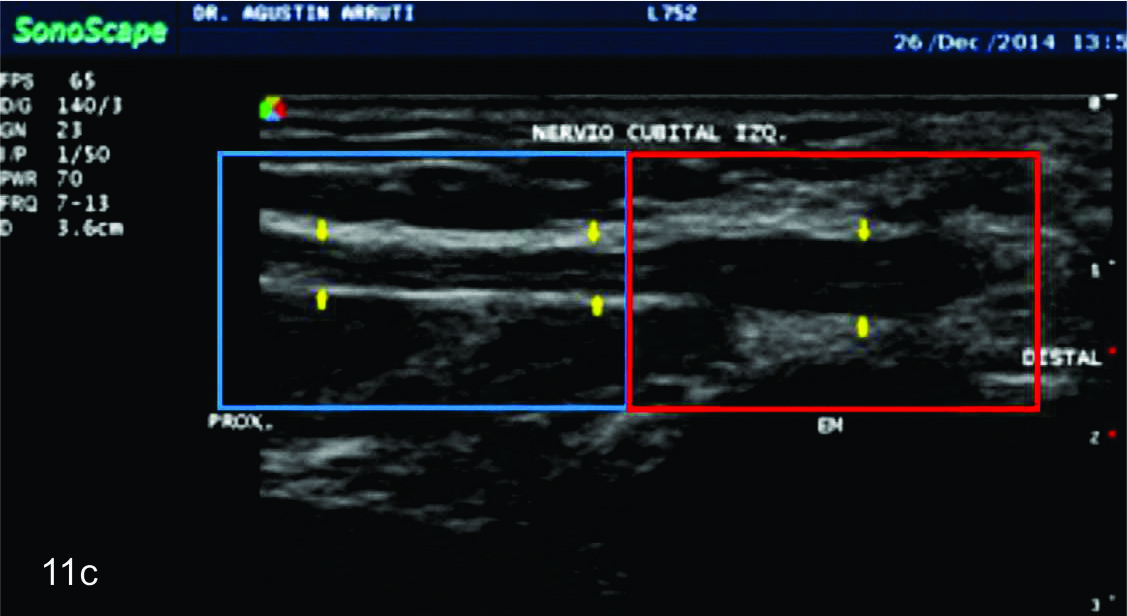

Figura 11

Inestabilidad del nervio cubital

A- Corte transversal comparativo en el túnel epitrocleo-olecraneano con el codo en extensión: se observa el nervio cubital (flechas amarillas) a izquierda se encuentra engrosado e hipoecogénico con pérdida del patrón fascícular habitual lo cual es compatible con signos de neuropatía. B-Corte transversal comparativo en el túnel epitrocleo-olecraneano con el codo en flexión: se observa como el nervio cubital (flechas amarillas) a izquierda tiende a subluxarse, mientras que a derecha tiene una situación normal. C-Corte longitudinal sobre el nervio cubital (flechas amarillas) izquierdo, se demuestra la transición entre el patrón nervioso normal en brazo (recuadro color azul) y el patrón nervioso neuropático en codo (recuadro color rojo). EM- Epitroclea medial, Flecha roja- Canal epitrocleo olecraneano, Asterisco- músculo tríceps.